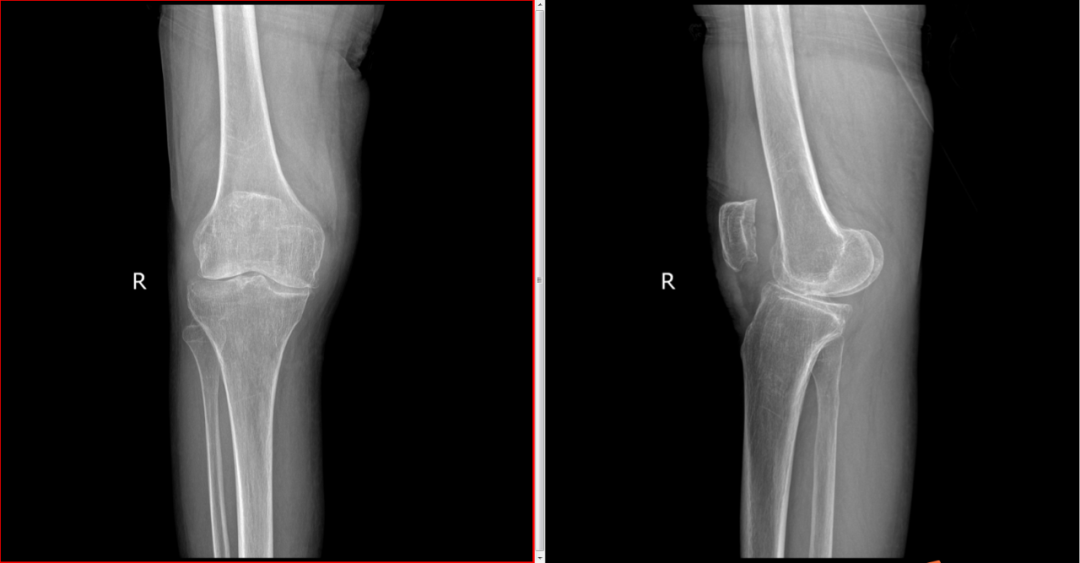

现年64岁的赵阿姨,右膝反弓步态走进科室,自述:右膝关节疼痛2年之久,行走时膝关节打软、无力,关节疼痛明显,屈伸受限。入院诊断:右膝关节骨性关节炎(IV期,反弓型)伴右侧腘静脉血栓形成、骨质疏松。

术前

术前DR片

“患者膝关节反弓,关节不稳,软骨磨损,随着年龄增大,关节的不稳定性和疼痛只会进一步加重!”付昆教授介绍,通过跟患者及家属沟通交流,在征得他们同意的情况下,计划为赵阿姨选择“内轴型人工全膝关节置换”。